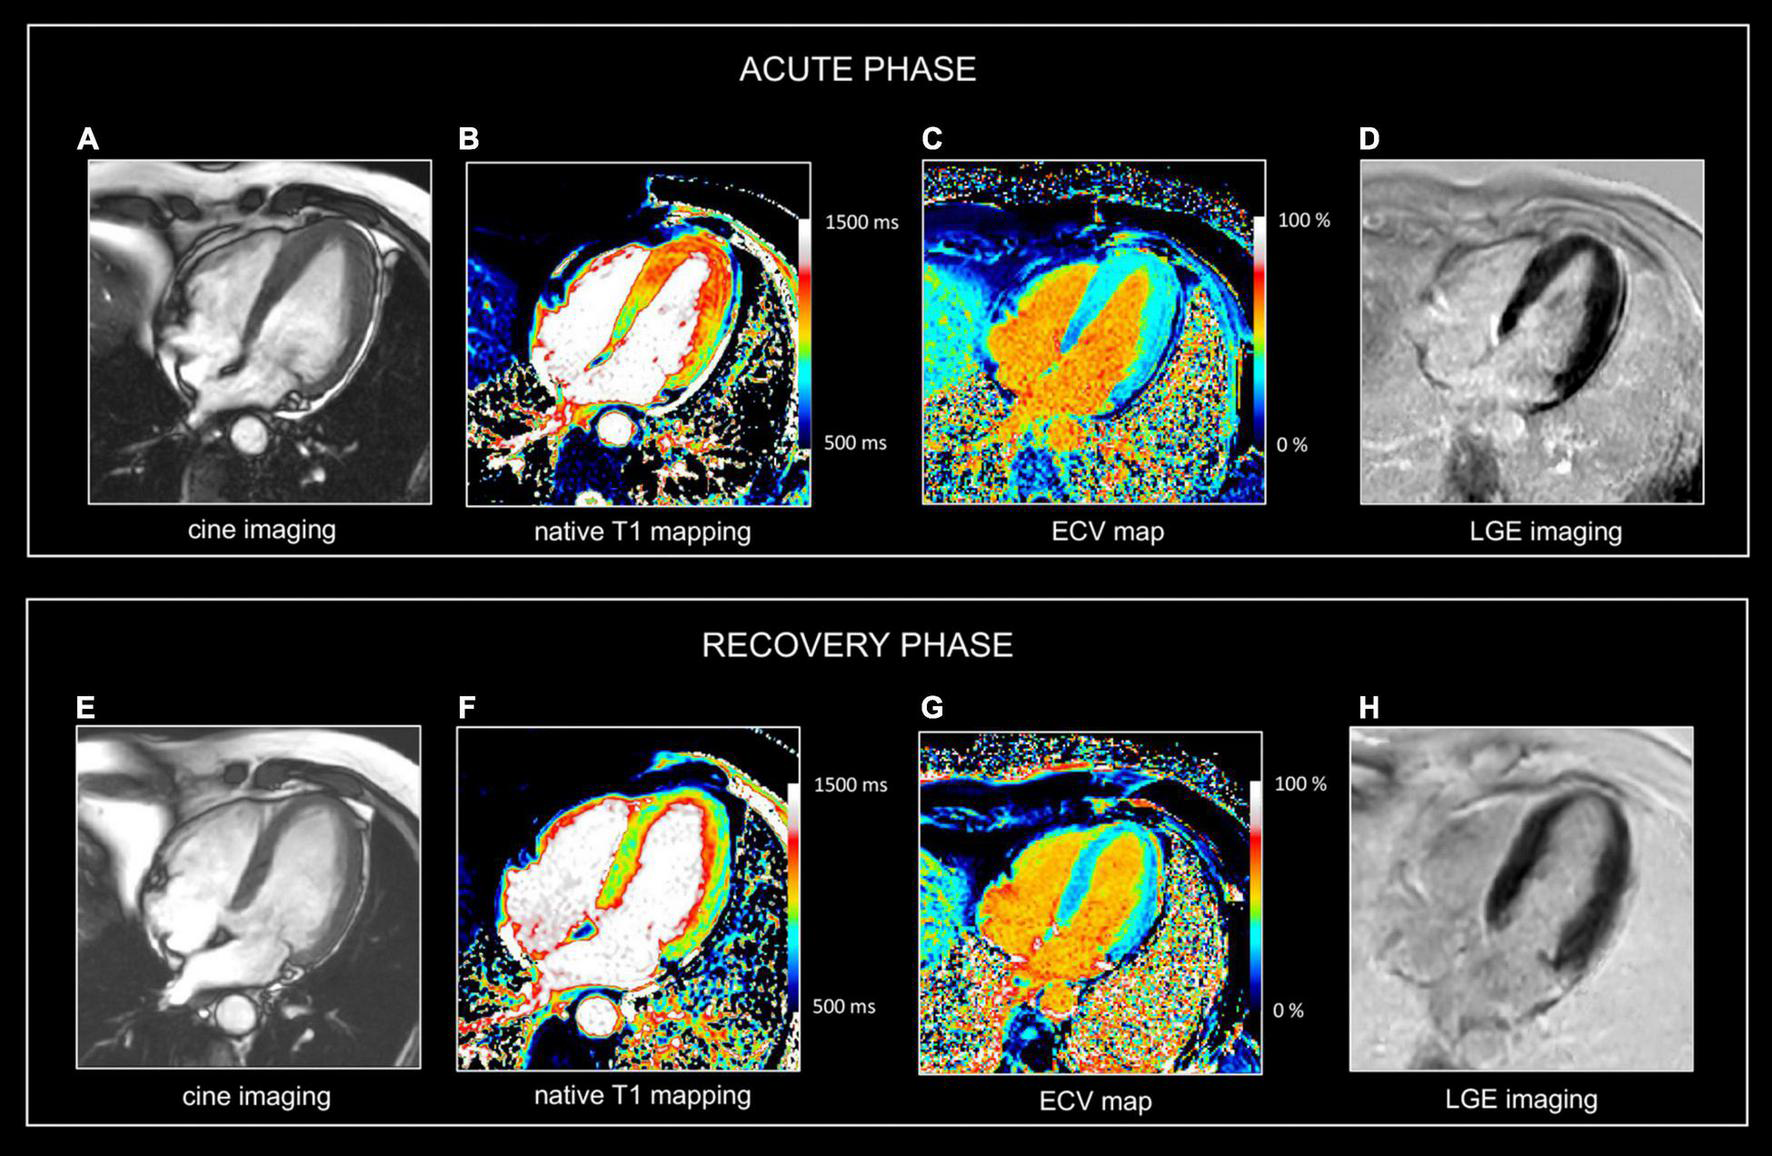

FIGURE 2

Use of CMR in acute and follow-up phase of diffuse myocarditis. Sixteen-year-old boy admitted with viral myocarditis and heart failure. Increased troponin I (12,239 ng/L), NTproBNP (23,731 ng/L) and c-reactive protein (183 mg/L). At admission, transthoracic echocardiography shows non-dilated but severely dysfunctional LV (EF 20%) and mild pericardial effusion. CMR, performed five days later, shows almost complete functional recovery (i.e., LV ejection fraction 57%). Although LGE imaging (D) shows no focal myocardial abnormalities, native T1, T2 and ECV values are diffusely increased, i.e., 1125 ms, 69 ms and 34% [panels (A–C), respectively]. Presence of limited pericardial effusion [arrow, (D)]. Repeat CMR 4 months later (recovery phase) shows normalization of T1, T2 and ECV values, i.e., 975 ms, 51 ms, and 24% [panels (E–G), respectively], while LGE imaging (H) yields no evidence of permanent irreversible damage (i.e., focal replacement fibrosis). Moreover, a further improvement in LVEF was noted, i.e., 64% with decrease in LV mass (i.e., 83 vs. 102 g at baseline), and disappearance of the pericardial effusion. In the clinical setting, the baseline CMR findings most likely represent diffuse myocardial edema/inflammation caused by viral myocarditis. As the myocardium is diffusely affected, weighted sequences, i.e., T2 and LGE imaging are “normal” emphasizing the added value of parametric mapping in these patients.